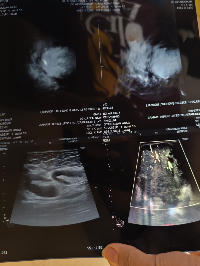

Eu sou a Yasmin e criei essa vakinha para ajudar no tratamento da minha irmã sara q descobriu o câncer de mama recentemente e precisamos de ajuda para pagar o tratamento dela q ficou em torno de 500mil começamos o tratamento mais precisamos de ajuda para continuar o tratamento quem puder nos ajudar agradeço de coração 🙏🏾